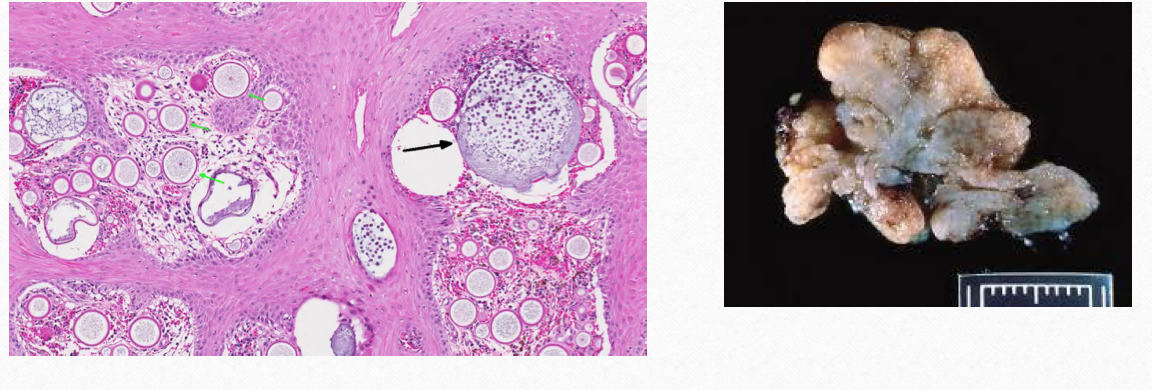

In the nasal cavity of a horse

Rhinosporidium